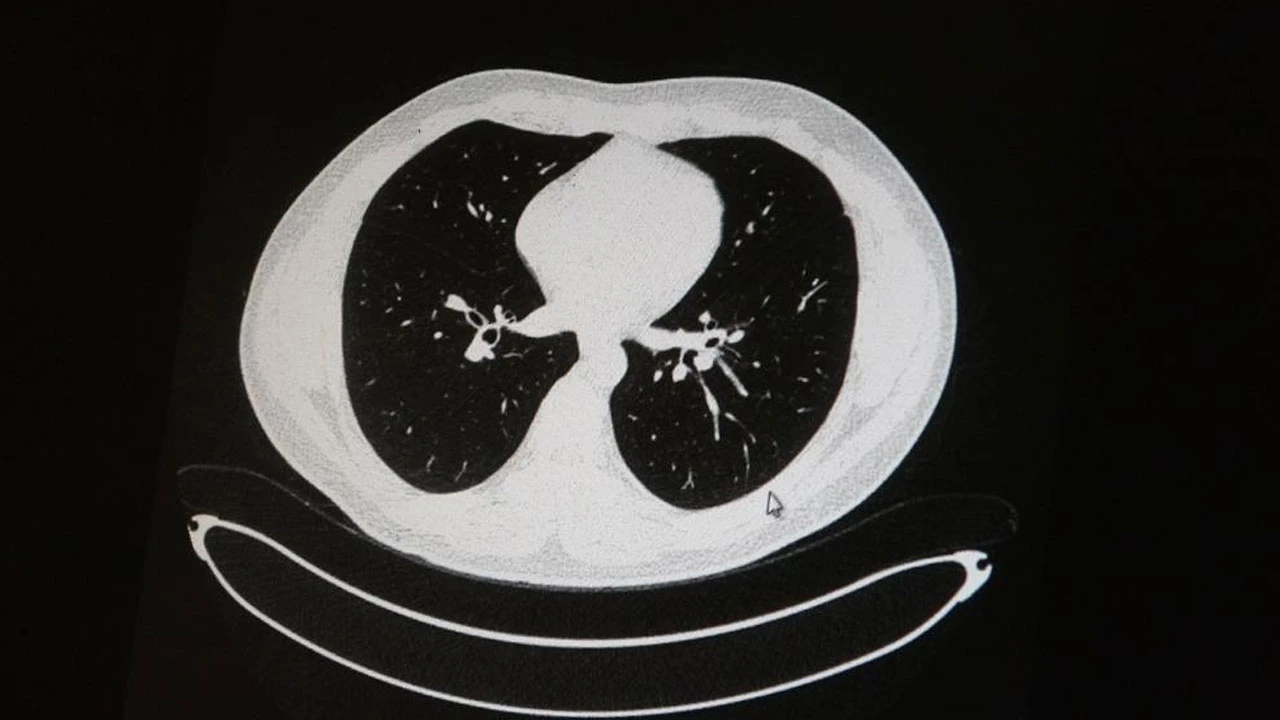

Koronavirüsün aşılı ve aşısızlarda bıraktığı ağır tahribat, akciğer tomografisinde net bir biçimde ortaya çıktı.

Medical Park Elazığ Hastanesi Göğüs Hastalıkları Uzmanı Dr. Cebrail Azar, geçtiğimiz yıla oranla yoğun bakımda yatan hastaların yaş ortalamasının 65'ten 35'lere kadar düştüğüne dikkat çekti. Genç olduğu halde aşı olmayanlarda hastalığın ağır seyrettiğini ifade eden Uzm. Dr. Azar, "Ben gencim, benim bağışıklık sistemim kuvvetli" diyen genç bir hastanın akciğerlerinde ciddi lekelenmelerin olduğunu ve korona virüs zatürresi olduğunu gördüklerini belirtti.

Uzm. Dr. Azar, aynı şekilde aşı olup korona virüs hastalığına yakalanan bir başka genç hastanın akciğer tomografisinde akciğerde herhangi bir sorunun olmadığını ve hastanın durumunun iyi olduğunu gözlemlediklerini kaydetti. Uzm. Dr. Azar, sürekli şahit oldukları "Keşke biz aşı olsaydık" sözünü bir daha duymamak için herkesi aşı olmaya davet etti.